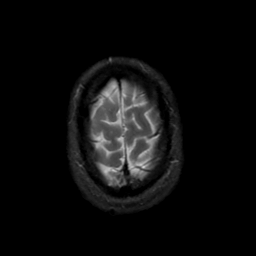

MR Study #20 October 6, 1991 -- Slice #45

[Home][Help][Clinical][Tour 1][Tour 2] Slice 45